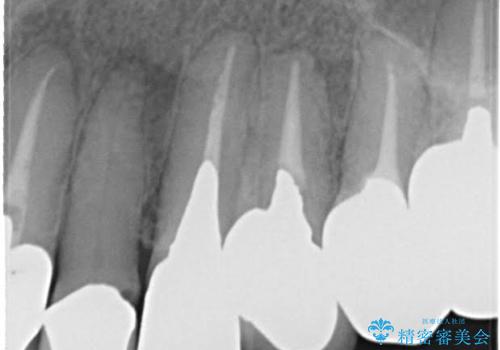

- 歯周外科・再根管治療後、クラウンを製作する。

・虫歯がとりきれていない

・接触部分がガタガタで適合の悪い金属

・全く無菌の努力がされていない根管治療

など、いい加減な治療は「治療」ではなく、むしろ医原性に歯の寿命を短くします。

最もよくないのは、クオリティの低い治療を何度も繰り返すことです。

時間をかけ、妥協なく治療を行い、今後の再治療の可能性を極力少なくするために、

費用や時間といった労力がかかってしまうのは当然のことです。